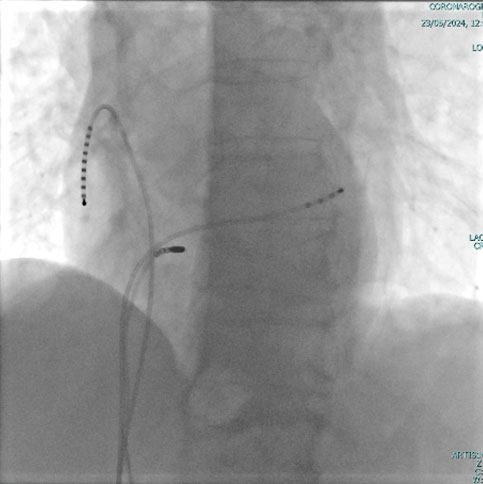

I pacemaker leadless possono essere posizionati nella cavità ventricolare ed eventualmente, atriale destra con una procedura mini invasiva per via transcatetere con approccio transcutaneo utilizzando la vena femorale (dall'inguine), attraverso uno speciale introduttore. Il sistema non richiede quindi la creazione di una tasca e non lascia cicatrici esterne visibili.

Questo nuovo tipo di Pacemaker è totalmente intracardiaco è formato da un dispositivo fissato direttamente all'interno del ventricolo destro, ed eventualmente atrio destro. Nel caso di un impianto bicamerale (atrio e ventricolo destro), grazie ad un innovativo sistema di comunicazione, i device riescono a “parlare“ tra di loro per sincronizzare le due camere cardiache. L'introduzione di questo tipo di tecnologia  leadless da inizio ad una nuova era del pacing intracardiaco.